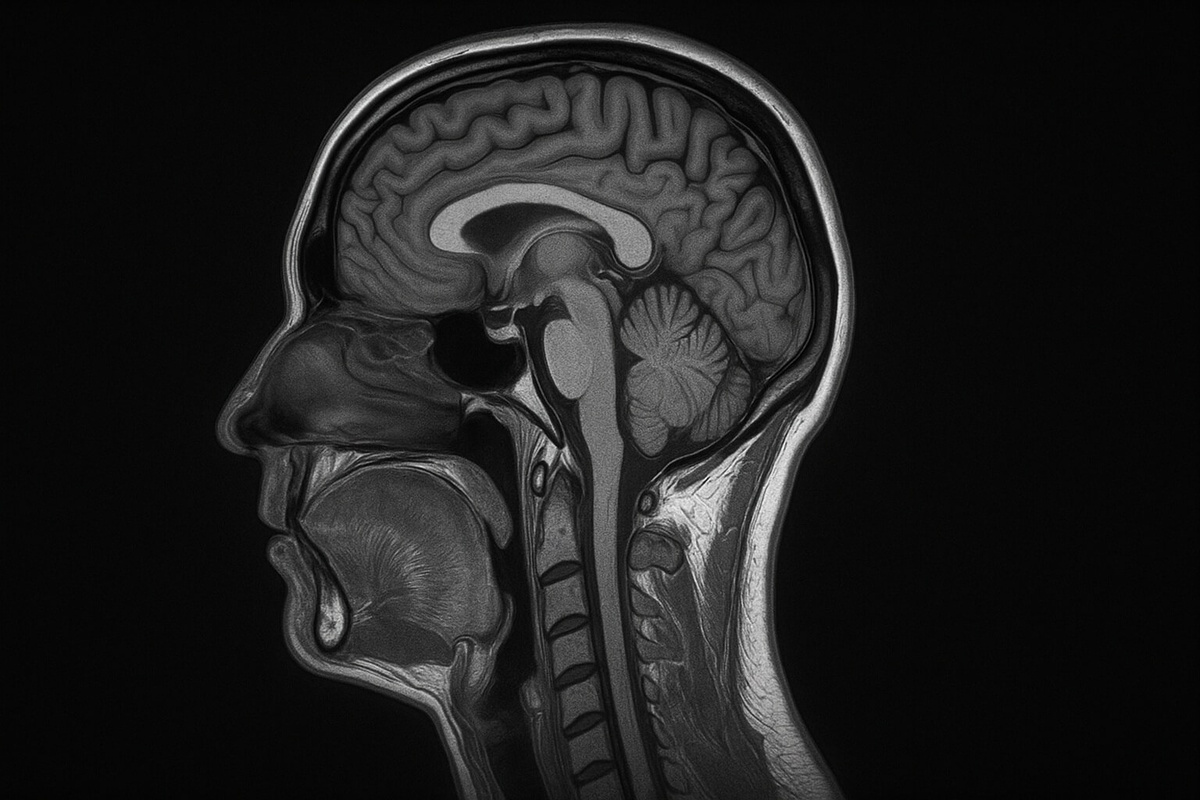

МРТ сегодня кажется чем-то привычным: пришел, лег в капсулу, полчаса потерпел шум и получил снимки, которые врач видит лучше любого рентгена. За этим процессом стоит мощнейший магнит, который буквально «слышит» атомы водорода в нашем теле и превращает их отклик в четкое изображение мозга, суставов или внутренних органов. Именно поэтому врачи обожают этот метод — он показывает то, что скрыто от глаз. Но перед прохождением МРТ людей просят оставить смартфон и многие другие предметы. И этому есть весомая причина.

Магнит в МРТ в тысячи раз мощнее бытовых магнитов и работает постоянно